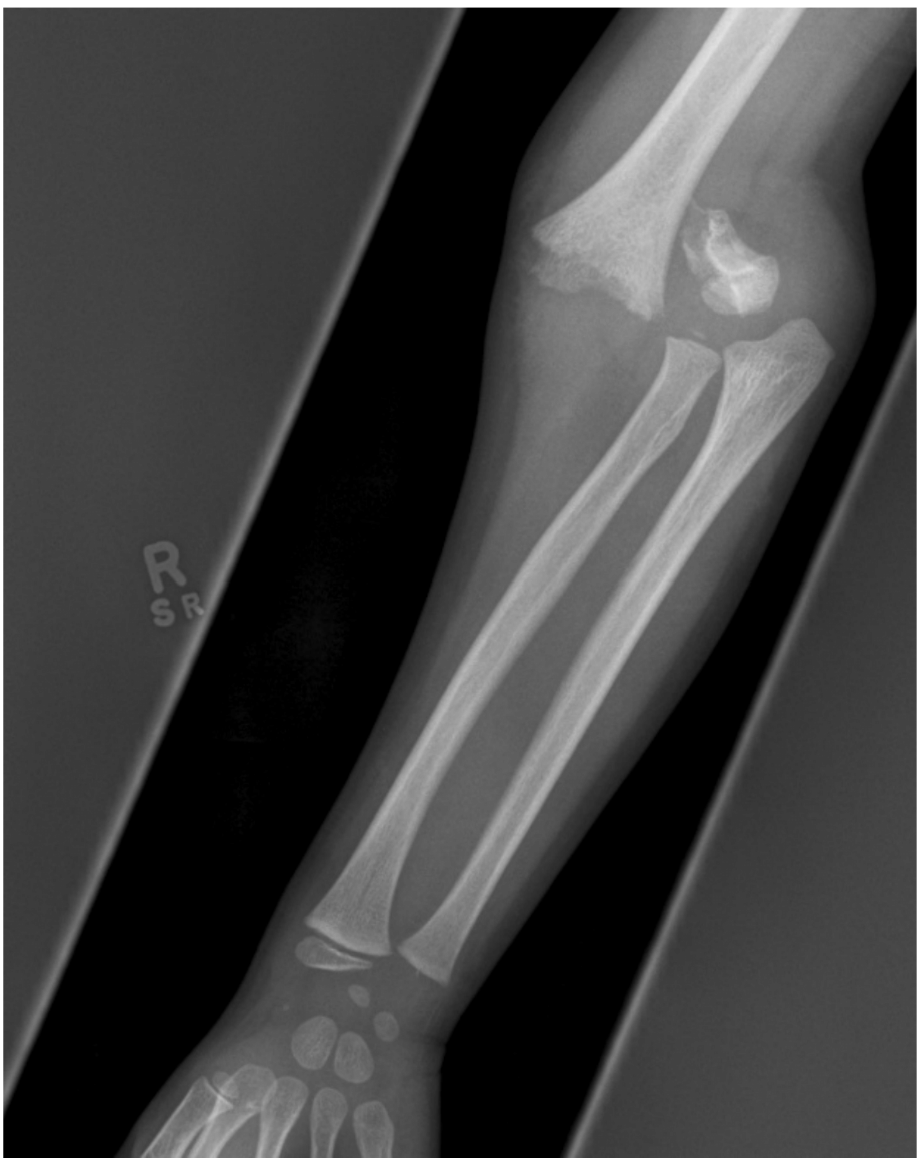

A 3 year old boy presents with right elbow pain following a fall from monkey bars.

An Xray is taken soon after arrival.

a. State four (4) abnormal findings shown on this Xray. (4 marks)

b. Assuming that there is neurovascular compromise, list five (5) steps to correct this problem. (5 marks)

c. List three (3) complications of this injury in the first 1 week post injury. (3 marks)